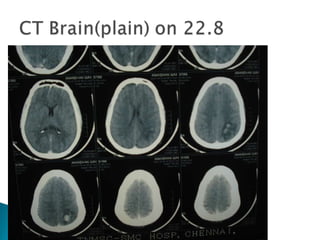

Seizure disorder for Evaluation (to r/o ICH) Treated with Inj.Phenytoin. Base line investigations : normal CT brain : multiple hemorrhagic infarct on both hemispheres

Bilateral fronto-parietal hemorrhagic infarct Filling defect noted in SSS- suggeting SSS thrombosis . Final Diagnosis: Dural Venous Sinus thrombosis

Rpt CT scan(12.8.09):ICH with midline shift(CT report Not available) Rpt CT scan(22.8) :Lt. parieto-occipital hemorrhagic infarct  MRI and MRV(22.8) : Lt. fronto parietal hemorrhagic infarct -Rt.tranverse, Rt.sigmoid and SSS thrombosis

. CT Infarction in nonarterial distribution (often hemorrhagic) Empty delta sign Dense triangle sign Cord sign DIRECT SIGNS

Direct sign : i. Cord sign :on plain CT, represents the spontaneous visualization of a thrombosed cortical vein; it’s rare . ii. Dense triangle sign :reflects spontaneous SSS opacification by freshly clotted blood iii. Empty delta sign : after contrast, it reflects the contrast between the opacified collateral veins in the SSS wall and non opacification of the clot inside the sinus.MC direct sign and seen approximately 35% of the cases.

Seizure disorder forEvaluation (to r/o ICH) Treated with Inj.Phenytoin. Base line investigations : normal CT brain : multiple hemorrhagic infarct on both hemispheres

Bilateral fronto-parietal hemorrhagicinfarct Filling defect noted in SSS- suggeting SSS thrombosis . Final Diagnosis: Dural Venous Sinus thrombosis

Rpt CT scan(12.8.09):ICHwith midline shift(CT report Not available) Rpt CT scan(22.8) :Lt. parieto-occipital hemorrhagic infarct MRI and MRV(22.8) : Lt. fronto parietal hemorrhagic infarct -Rt.tranverse, Rt.sigmoid and SSS thrombosis

. CT Infarctionin nonarterial distribution (often hemorrhagic) Empty delta sign Dense triangle sign Cord sign DIRECT SIGNS

Direct sign :i. Cord sign :on plain CT, represents the spontaneous visualization of a thrombosed cortical vein; it’s rare . ii. Dense triangle sign :reflects spontaneous SSS opacification by freshly clotted blood iii. Empty delta sign : after contrast, it reflects the contrast between the opacified collateral veins in the SSS wall and non opacification of the clot inside the sinus.MC direct sign and seen approximately 35% of the cases.